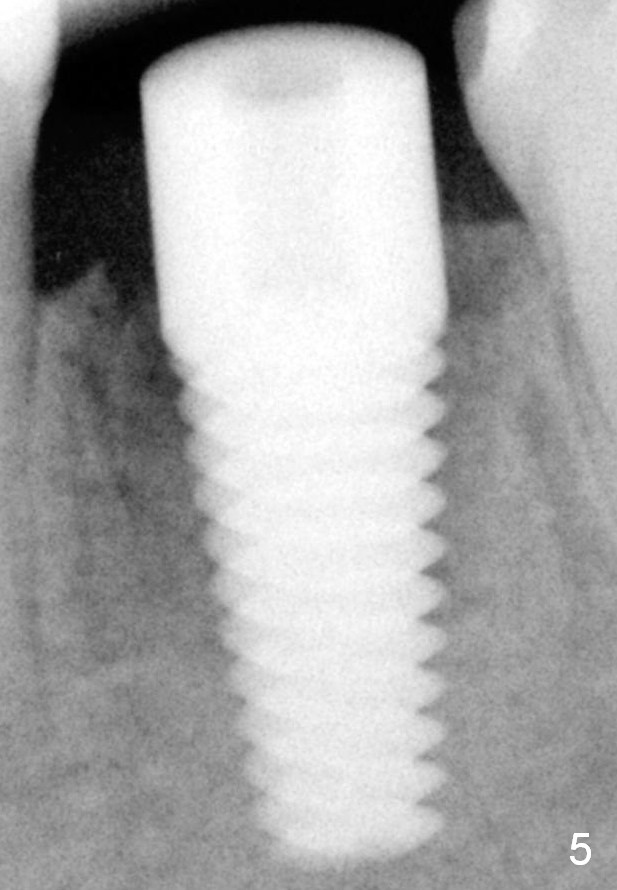

Fig.5 (immediately postop): A 6x17 mm implant is placed.